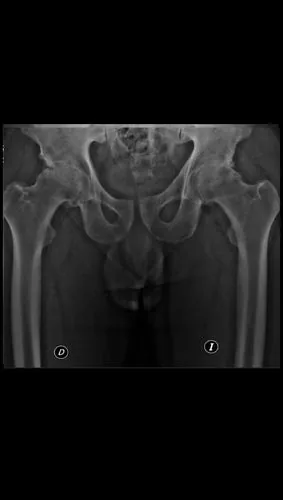

Preoperatorio

Artroplastia total bilateral de cadera en un solo tiempo quirúrgico. Alta hospitalaria a las 24 horas, deambulando con andador. Excelente restauración de la biomecánica articular bilateral.